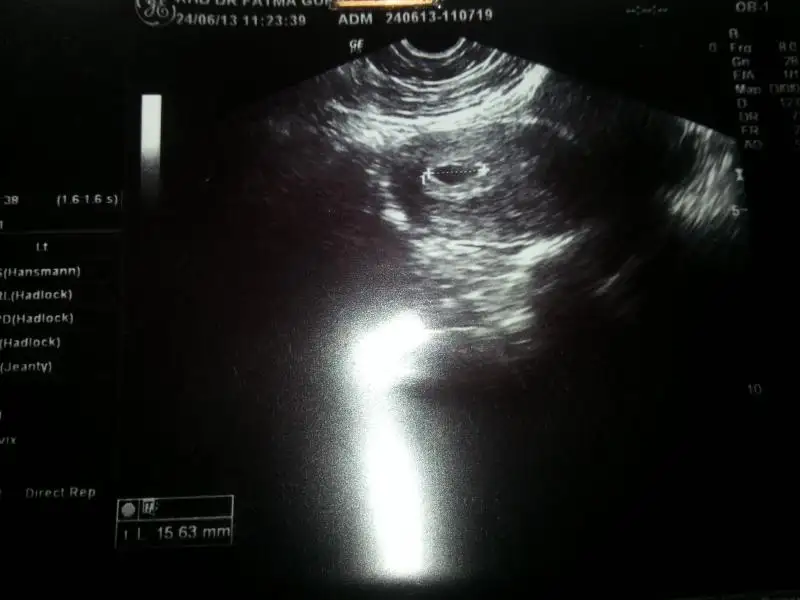

o işaretli yer nere kese çapı dimiii. dedim acaba kafatası mı

canım fotoda sağa yakın yani içinde sola...içinde soldaysa kızdırgelin kaynana toprağından olurmuş ben de soldaymışım